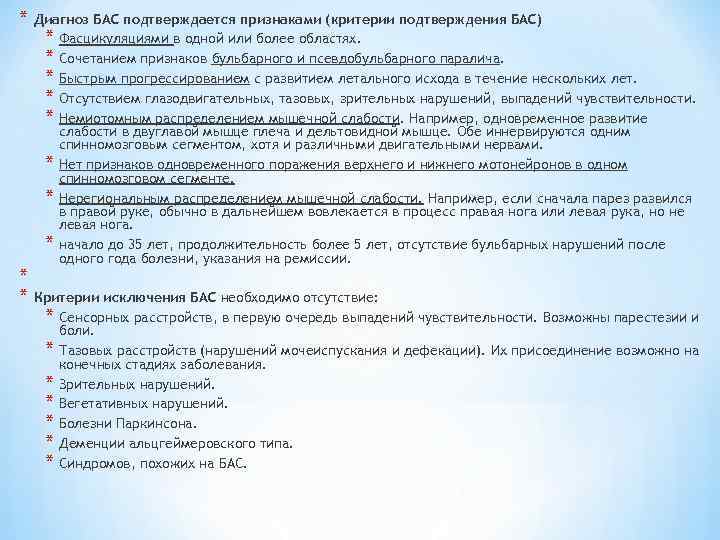

* Диагноз БАС подтверждается признаками (критерии подтверждения БАС) * Фасцикуляциями в одной или более областях. * Сочетанием признаков бульбарного и псевдобульбарного паралича. * Быстрым прогрессированием с развитием летального исхода в течение нескольких лет. * Отсутствием глазодвигательных, тазовых, зрительных нарушений, выпадений чувствительности. * Немиотомным распределением мышечной слабости. Например, одновременное развитие * * * слабости в двуглавой мышце плеча и дельтовидной мышце. Обе иннервируются одним спинномозговым сегментом, хотя и различными двигательными нервами. Нет признаков одновременного поражения верхнего и нижнего мотонейронов в одном спинномозговом сегменте. Нерегиональным распределением мышечной слабости. Например, если сначала парез развился в правой руке, обычно в дальнейшем вовлекается в процесс правая нога или левая рука, но не левая нога. начало до 35 лет, продолжительность более 5 лет, отсутствие бульбарных нарушений после одного года болезни, указания на ремиссии. * * Критерии исключения БАС необходимо отсутствие: * Сенсорных расстройств, в первую очередь выпадений чувствительности. Возможны парестезии и * * * боли. Тазовых расстройств (нарушений мочеиспускания и дефекации). Их присоединение возможно на конечных стадиях заболевания. Зрительных нарушений. Вегетативных нарушений. Болезни Паркинсона. Деменции альцгеймеровского типа. Синдромов, похожих на БАС.

* Диагноз БАС подтверждается признаками (критерии подтверждения БАС) * Фасцикуляциями в одной или более областях. * Сочетанием признаков бульбарного и псевдобульбарного паралича. * Быстрым прогрессированием с развитием летального исхода в течение нескольких лет. * Отсутствием глазодвигательных, тазовых, зрительных нарушений, выпадений чувствительности. * Немиотомным распределением мышечной слабости. Например, одновременное развитие * * * слабости в двуглавой мышце плеча и дельтовидной мышце. Обе иннервируются одним спинномозговым сегментом, хотя и различными двигательными нервами. Нет признаков одновременного поражения верхнего и нижнего мотонейронов в одном спинномозговом сегменте. Нерегиональным распределением мышечной слабости. Например, если сначала парез развился в правой руке, обычно в дальнейшем вовлекается в процесс правая нога или левая рука, но не левая нога. начало до 35 лет, продолжительность более 5 лет, отсутствие бульбарных нарушений после одного года болезни, указания на ремиссии. * * Критерии исключения БАС необходимо отсутствие: * Сенсорных расстройств, в первую очередь выпадений чувствительности. Возможны парестезии и * * * боли. Тазовых расстройств (нарушений мочеиспускания и дефекации). Их присоединение возможно на конечных стадиях заболевания. Зрительных нарушений. Вегетативных нарушений. Болезни Паркинсона. Деменции альцгеймеровского типа. Синдромов, похожих на БАС.